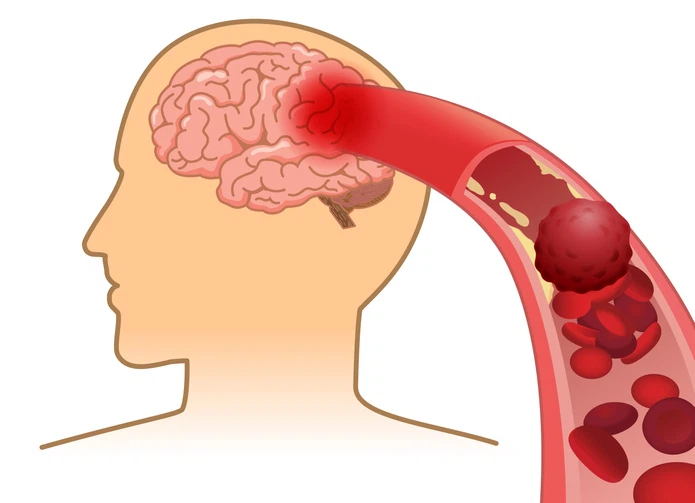

뇌졸중은 뇌에 혈액을 보급하는 혈관이 차단되거나 파손되어 뇌 손상과 인체장애를 일으키는 뇌혈관 질환을 말하고

'중풍' 이나 '뇌혈관 질환'이라고 알려진 게 바로 뇌졸중입니다. 뇌경색이란 용어도 자주 듣게 되는데 뇌경색과 뇌출혈은 뇌졸중의 한 종류로 뇌졸중 중에 뇌경색, 뇌출혈이 포함된다고 볼 수 있습니다.